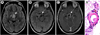

Polymer substances are commonly applied as surface coatings on endovascular catheters and vascular devices. Adverse effects related to their use have been reported, although the overall clinical significance and appropriate methods of detection of these complications have been unclear. In this analysis, we systematically reviewed clinical and diagnostic features in 32 patients (age, 36-87years; mean, 59years) in whom intracranial polymer reactions were documented following vascular interventions. Associated neuroradiologic and neuropathologic findings were variable and included cerebral vasculitis or vasculopathy (63%), abscess or granuloma formation (38%), ischemic infarcts (28%), parenchymal hematomas (28%), white matter change (25%), and/or chemical meningitis (22%). Location(s) of polymer reactions varied and included sites adjacent to and/or downstream from instrument insertion or implantation. Presenting clinical signs included focal neurologic deficits (41%), headache (22%), constitutional symptoms (19%), meningitis (16%), seizure and/or involuntary movements (9%), coma (6%), and syncope (3%). Adverse outcomes included stroke (31%), death (28%), delayed communicating hydrocephalus (9%), steroid dependency (9%), steroid complications (6%), and cerebral volume loss (3%). In some cases, these complications necessitated increased cost and length of medical care. In this review, we highlight the diverse features of polymer-induced reactions involving the central nervous system and summarize distinct diagnostic patterns that may enable earlier premortem detection of these lesions in the postprocedural clinical setting. Further work in this area is necessary to identify additional etiologic, preventative and therapeutic strategies. These data have potentially broad implications pertaining to the safety, efficacy, standards of use, storage, manufacturing, and regulation of new and emerging vascular devices and polymer nanotechnologies.